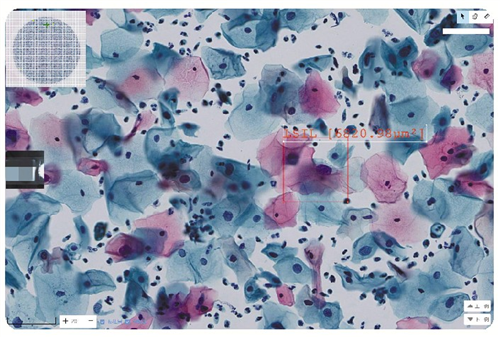

通过不断的积累临床案例,以及算法模型的不断演进,AI逐渐成长为病理医生的助手。目前,AI已在宫颈液基细胞学应用上“学有所成”。

在病理科细胞学组,医生刘俊许、杜丹凤、张士岭在对AI筛选出的“阳性”病例进行复核。“每个切片里可能有两三万个细胞,要用肉眼逐一检查,耗费的时间和精力相当庞大。”关于AI在细胞学诊断的准确性,病理医生的反馈是“AI是一位非常严苛的助手,它判定‘阳性’的标准相对较低,宫颈细胞核形态或者浆比稍有异常,就会定为‘阳性’,并将可疑的病变细胞圈注出来提醒医生关注”。

该院病理科利用两年时间,AI阴性诊断准确率接近100%,排阴率接近80%。

排阴率为什么这么重要?李晓梅指出,筛查针对的是一般人群,也就是说,阴性病例占绝大多数,约90%。如果AI先把阴性病例准确诊断出来,那么病理医生可以有更多的时间对所有阳性或者可疑的阳性病例进行分析、判断最终形成准确的病理诊断,就能大幅减低工作量,“更重要的是,能让病理医生腾出更多时间、精力去处理其他疑难复杂的病例。”对于阴性病例,病理医生也是要进行复核,但在AI的协助下会大大节约诊断时间。